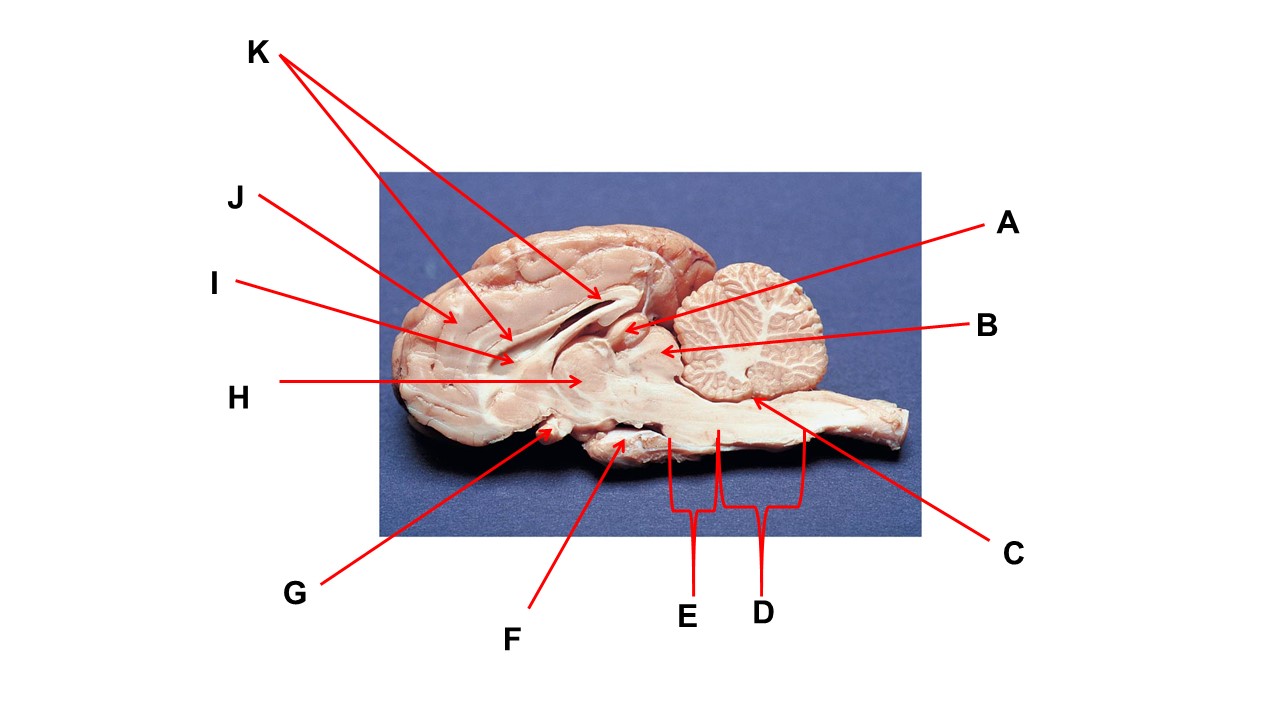

Name the structure at the tip of arrow A.

pineal gland

The cavity at the tip of arrow I is the _____.

lateral ventricular

The cavity at the tip of arrow I is filled with ______.

cerebrospinal fluid

Name the region within bracket D

medulla

Name the structure at the tip of arrow F

mammillary body

Name the structure at the tip of arrow A.

pineal gland

Name the structure at the tip of arrow G

optic chiasma

Name the nerve at the tip of arrow H.

optic